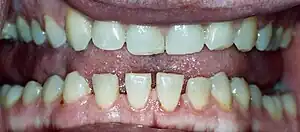

| Lower jaw showing the classic spacing of teeth due to acromegaly. | |

- Pronounced lower jaw protrusion (prognathism) with attendant macroglossia (enlargement of the tongue) and teeth spacing